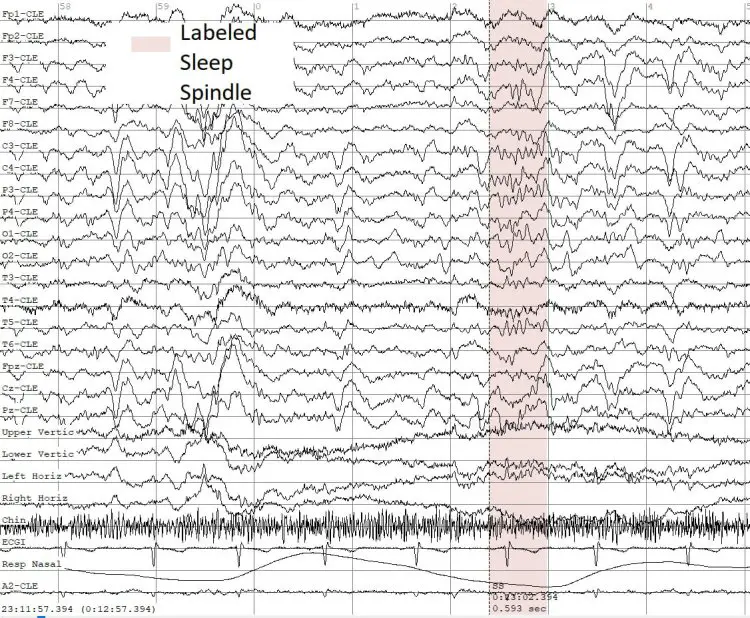

Одна из наиболее значимых задач, решаемых командой ННГУ под руководством Татьяны Левановой, заключается в изучении феномена сонных веретён — характерных для второй фазы сна ритмов, играющих ключевую роль в формировании воспоминаний и обучении. Эти ритмы считаются своеобразными «метками» для оценки важных когнитивных функций. У людей, страдающих эпилепсией, параметры «сонных веретён» часто нарушены: меняются их плотность, длительность, частота появления. Поэтому автоматический анализ этих биомаркеров становится крайне востребованным инструментом, повышающим качество медицинских решений.

Разработанный системой прототип искусственного интеллекта базируется на большом массиве качественно размеченных данных ЭЭГ, собранных совместно с врачами неврологами Артёмом Шарковым, Альбиной Лебедевой и клиницистами из Москвы и Нижнего Новгорода. Все решения, предлагаемые программой, проходят строгую верификацию у опытных специалистов. Это гарантирует клиническую применимость рекомендаций и способствует постоянному увеличению точности алгоритмов. Ведется масштабная работа по накоплению новых ЭЭГ-записей различных типов эпилептической активности, что позволяет регулярно совершенствовать анализ и предоставлять врачам все более надежные подсказки.